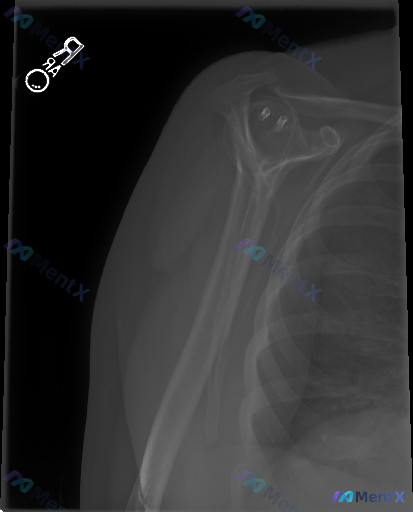

整理到一张右肩关节的X光片资料,标注有"RA",核心发现是肩胛盂边缘有两个明显的圆形高密度影,符合金属缝合锚钉的表现。 目前从片子上看: - 肱骨头和肩胛盂对位基本正常,没有明确急性骨折线或脱位 - 盂肱关节间隙宽度大致正常,没有明显骨赘或骨质破坏 - 肩峰下间隙清晰,没有异常钙化影 但问题在于,X...